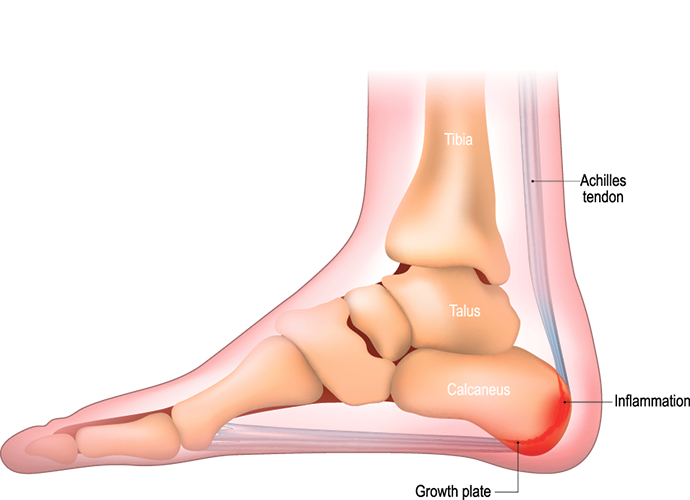

- Severs (kun hos børn)